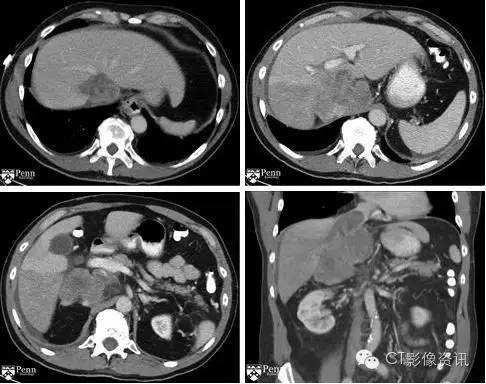

病史:64岁男性,腹痛

腹盆增强CT显示如下